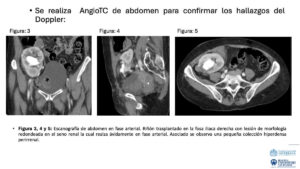

PE_015_Jose David Brito_04